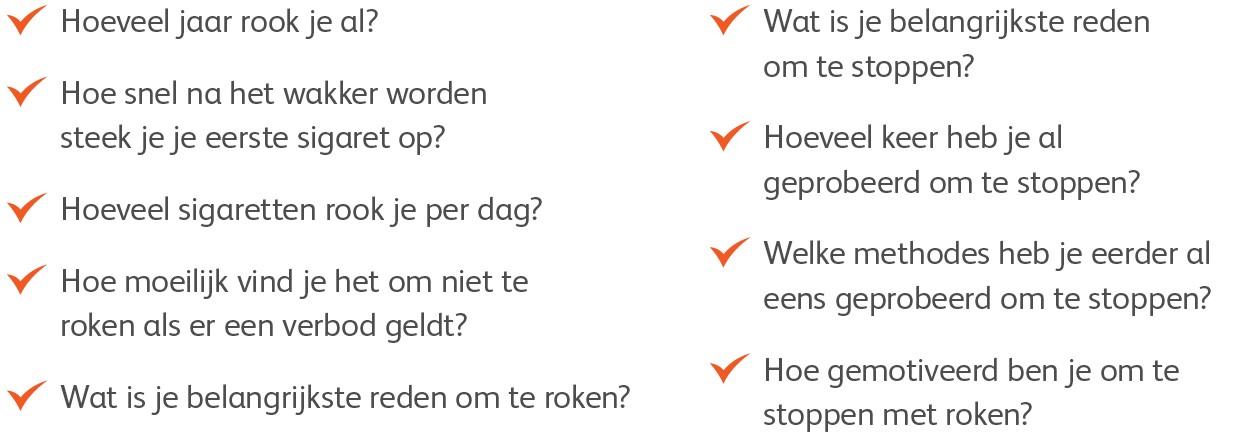

De diagnose

Voordat de diagnose amyloïdose gesteld is, heeft de patiënt vaak al een lange reis langs verschillende specialisten achter de rug. Herkent u - vanuit uw kennis en expertise als neuroloog, internist, nefroloog of cardioloog - de patronen van klachten? In gesprek met Monique Minnema, (internist-hematoloog, UMC Utrecht) en Hans Nienhuis (klinisch immunoloog/internist, UMCG).